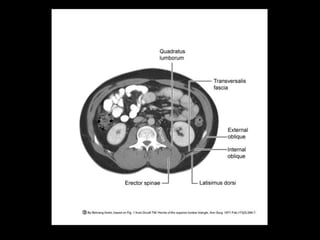

Hernias lumbares

• -2%

Congénitas 10%

Grynfelt : Tríangulo superior de la región lumbar

Petit: Triángulo inferior

Traumáticas 25%

Fracturas costales múltiples con lesión de Nervios IC 11 y 12 y

con trauma asociado a cinturón de seguridad

Incisionales 50-60%

Cirugía urológica con lumbotomía y qx ortopédica por la toma

de grandes porciones de la cresta iliaca para injerto de hueso

Espontáneas

Trastornos neurológicos con atrofia muscular de la región

lumbar